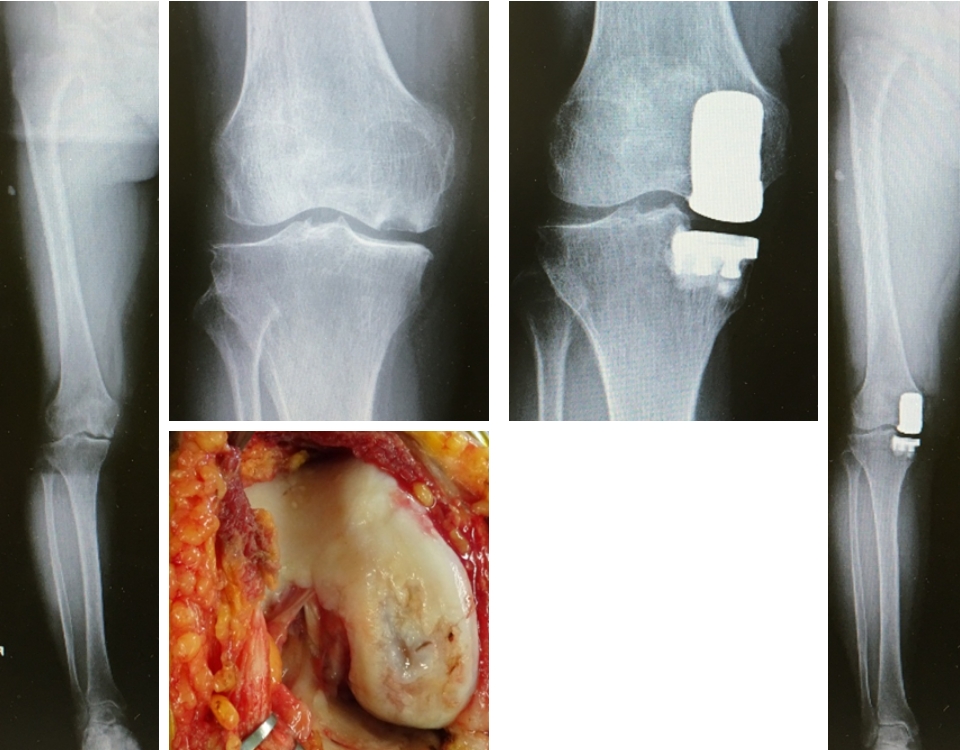

RAの前足部変形に対する関節温存手術

RAの前足部障害は多く認められ、末期には中足骨頭が底側に脱臼し、足底に胼胝を形成します。治療は脱臼した中足骨頭を切除する切除関節形成術が行われていましたが、近年薬物による関節修復の可能性や関節機能を再獲得する目的で関節を温存する手技に変わりました。手技は左図のように中足骨骨幹部遠位を短縮骨切り後、中足骨頭を近位へ引っ張り脱臼を整復して関節を温存します(図12)。これにより可動域や踏み返しが可能となり除痛、さらに地面をとらえた良好な歩容を目指します。

図12 RAに対する関節温存手術